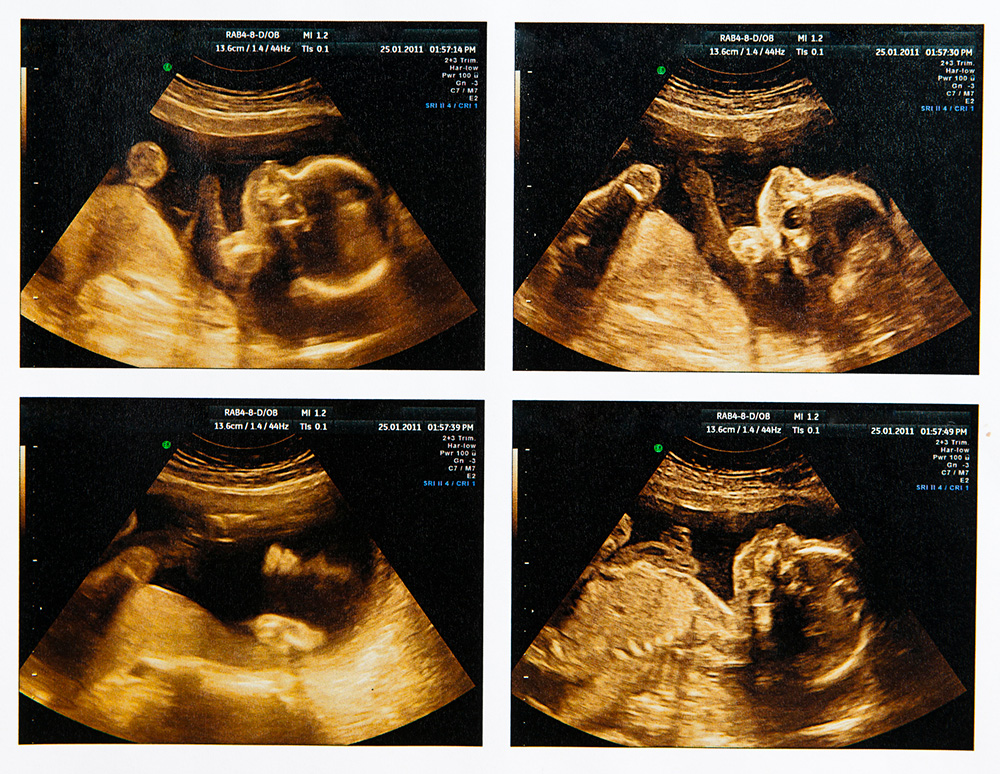

Wilson also offers a perspicacious consideration of how, in a society like ours, we might minimally ensure that all involved parties in this matter are taking on the decision with the requisite moral seriousness. He says that human beings use many sources of information to make decisions about what things are and are not persons, and one of those sources —a particularly important one for a highly ocularly-oriented species like ours —involves visual evidence. Now that ultrasound imagery of fetuses is so cheaply and easily obtainable, he suggests, we might want to require all women considering abortion to look at such images of what is in their wombs, to help fill out their base of knowledge and moral decision-making.